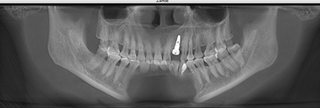

麦芽口腔硕博种牙团在了解到邓女士的情况后,对口腔全景ct深度分析,邓女士的剩下的牙齿残根已经无法再满足做普通的牙齿的美学修复,只有拔除剩下的残根,做种植牙才是最佳的牙齿修复的方式。麦芽硕博团为邓女士选择麦芽数字化生物种植牙保证口腔功能重建和舒适修复的同时,兼顾口腔美学修复,既能快速修复牙齿,恢复咀嚼,同时能够达到较好的美观程度,术中采用STA美国微痛麻醉,确保了手术全程的舒适度,且采用数字化3D种植导板技术,能够更加准确、更加快速找到最佳植入位置,有效避免手术过程遭受痛苦,保证了手术成功率。

种牙后的牙齿情况